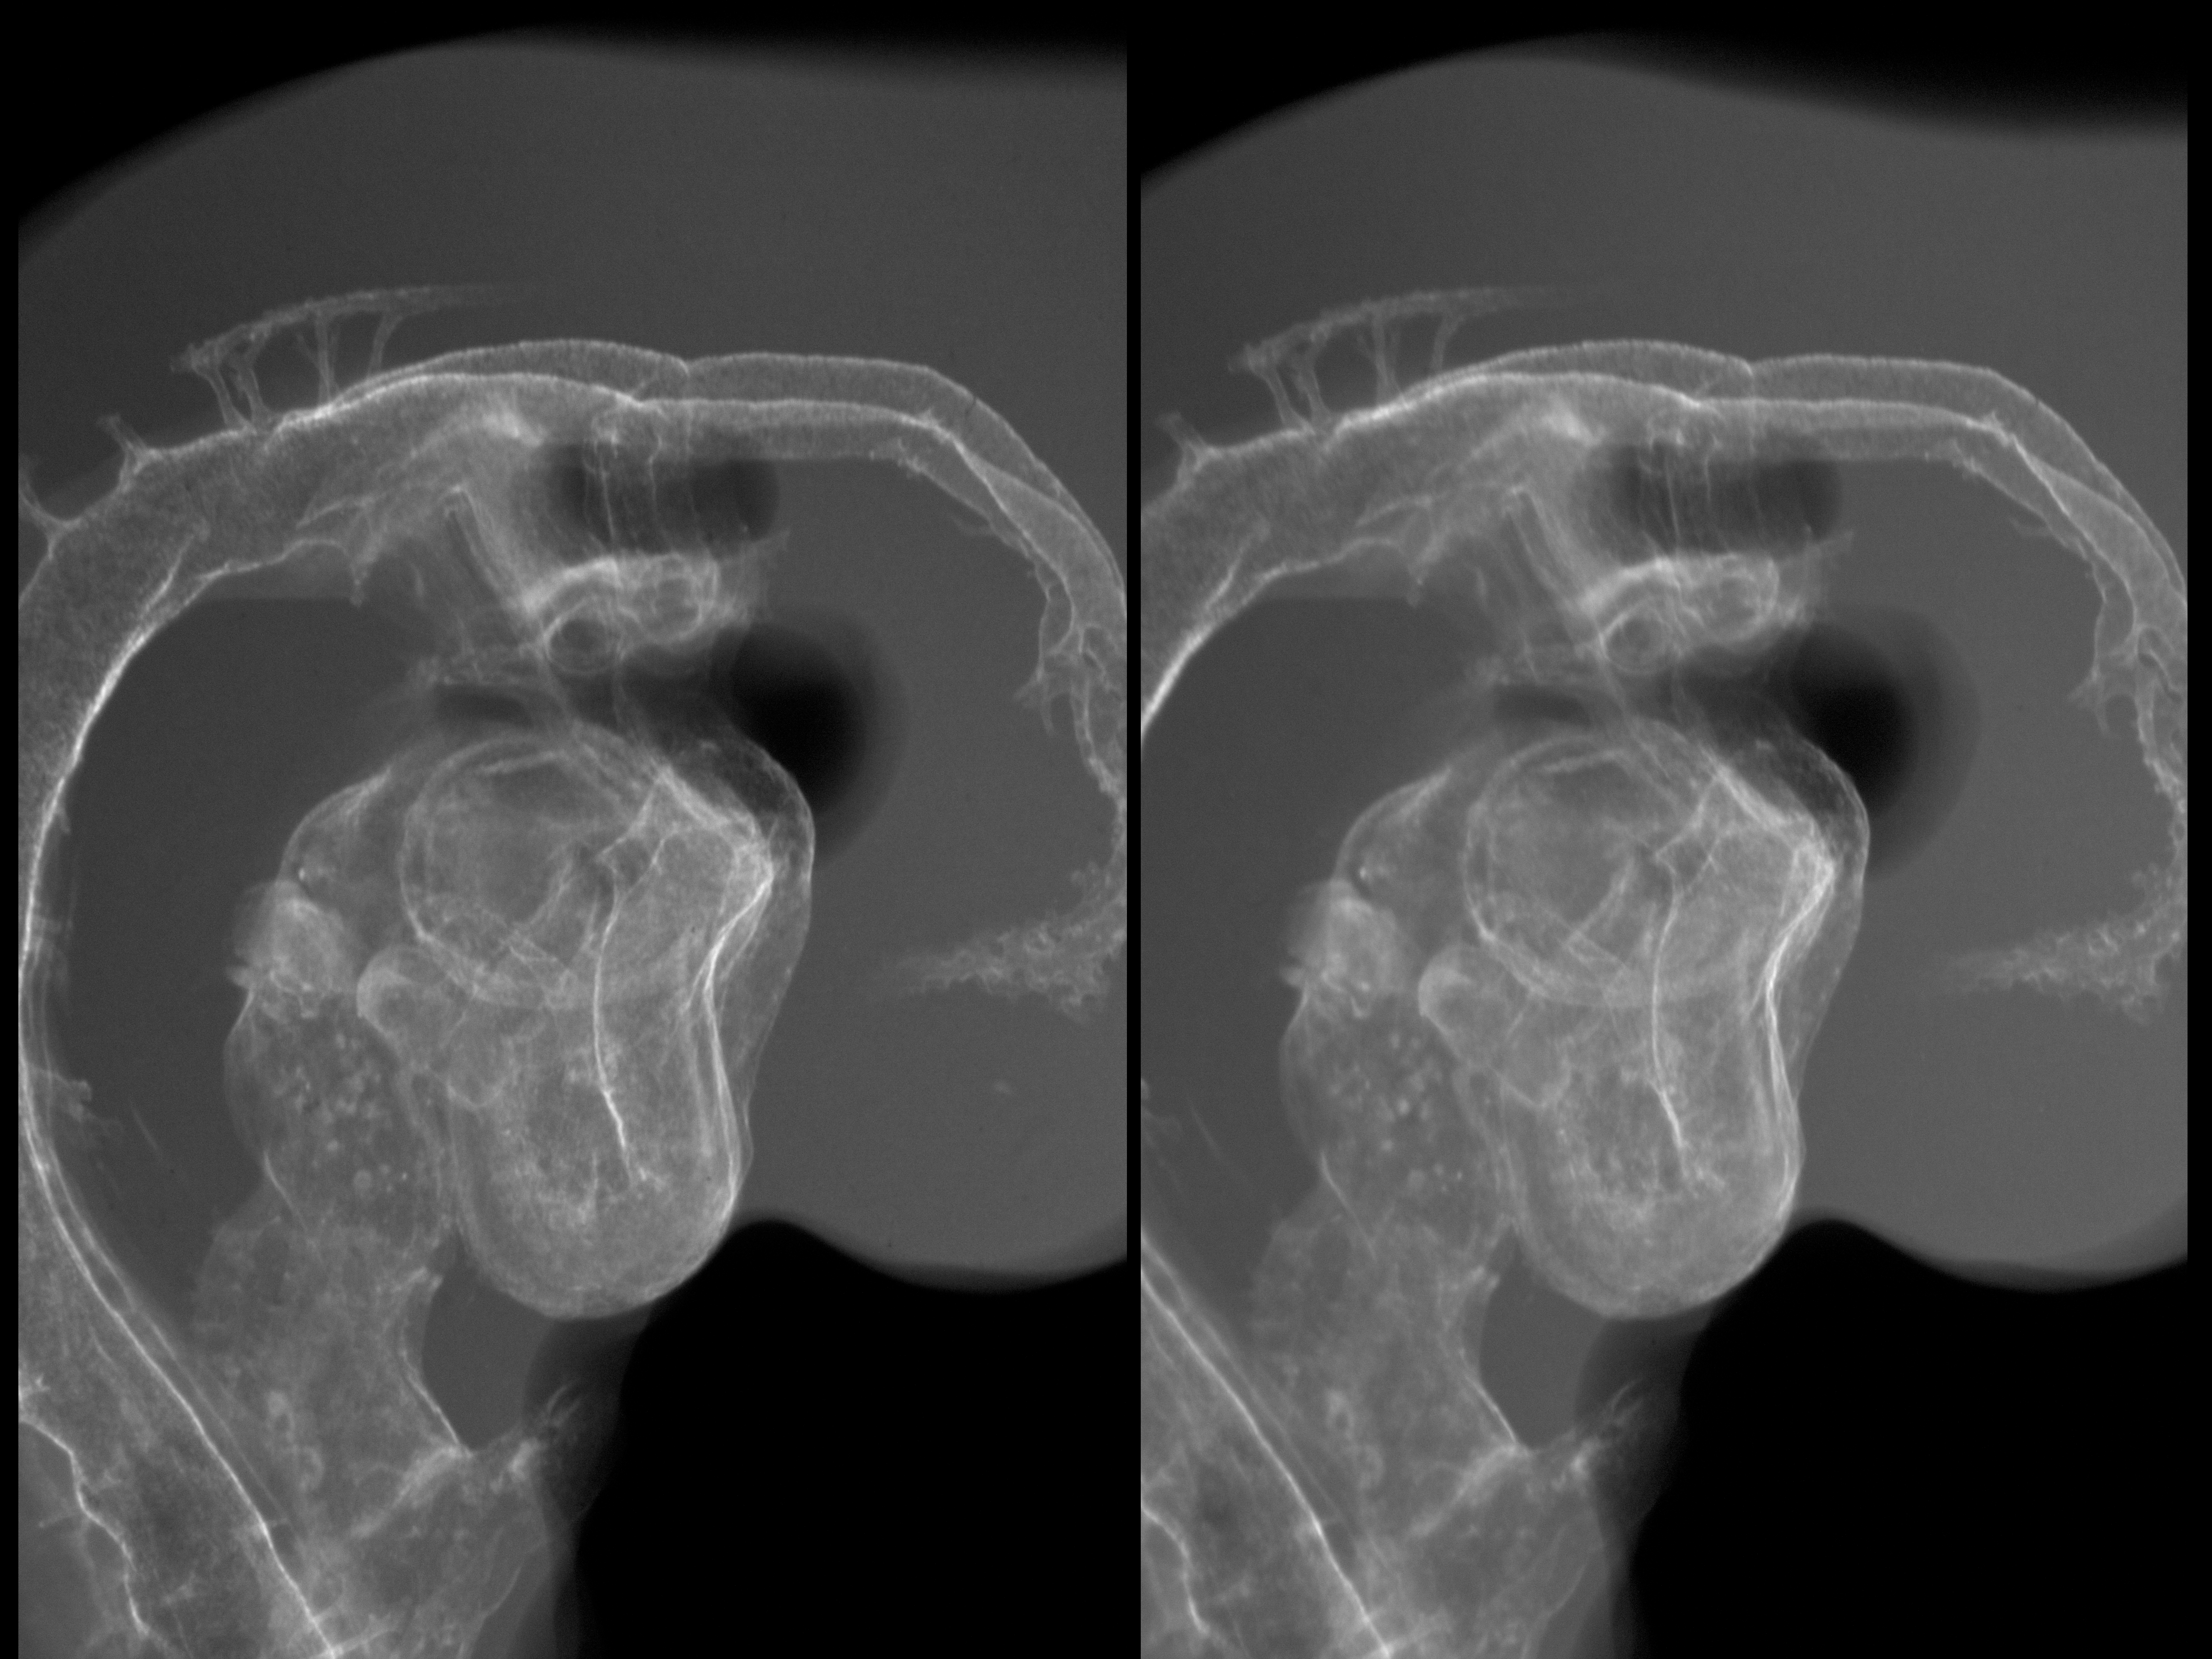

Chick Embryo Microangiography

Hamburger-Hamilton (HH) Stage 19 (approx. 3 - 3.5 days)

X-Ray Micrographs

Stereo X-Ray Micrographs